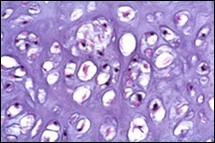

Distinction between benign cartilaginous lesions and atypical cartilaginous tumour or grade 1chondrosarcoma (ACT/CS1) can be challenging, Typically, benign cartilaginous lesions are hypo-cellular, in contrast to hyper-cellular atypical cartilaginous tumour or grade 1 chondrosarcoma 5, 6. Figure 1, Figure 2, Figure 3, Figure 4, Figure 5, Figure 6, Figure 7, Figure 8.

Figure 4.Enchondroma depicting lobules of hyaline cartilage with vacuolated cells and eccentric nuclei 12.

Figure 5.Enchondroma enunciating lobules of uniform cartilaginous cells with regular, centric nuclei and absence of mitosis 13.

Figure 6.Enchondroma exemplifying lobules of hyaline cartilage composed of enlarged, vacuolated cells with uniform nuclei. Focal calcification is absent 14